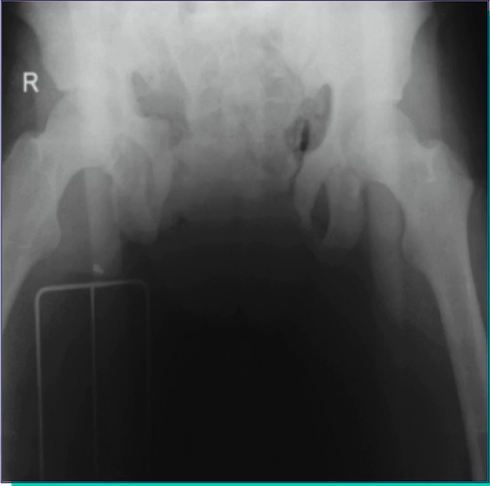

O que se observa na imagem?

• Quais as estruturas comprometidas?

• É grave?

• Qual a conduta?

A

Trauma de pelve em livro aberto

• Ruptura do plexo venoso posterior e ramos arteriais da ilíaca interna

• HEMORRAGIA PODE SER FATAL

• Seguir fluxograma de trauma pélvico